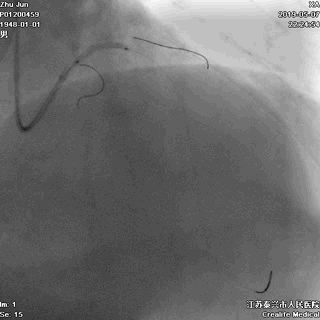

游离一根导丝至升主动脉,防止导管深插

轻轻冒烟,证实指引导管到位

轻轻冒烟,大致了解前降支的情况

这一步相当重要。否则,无论是导管嵌顿,还是导管深插,稍不留意患者都有可能一招致命。